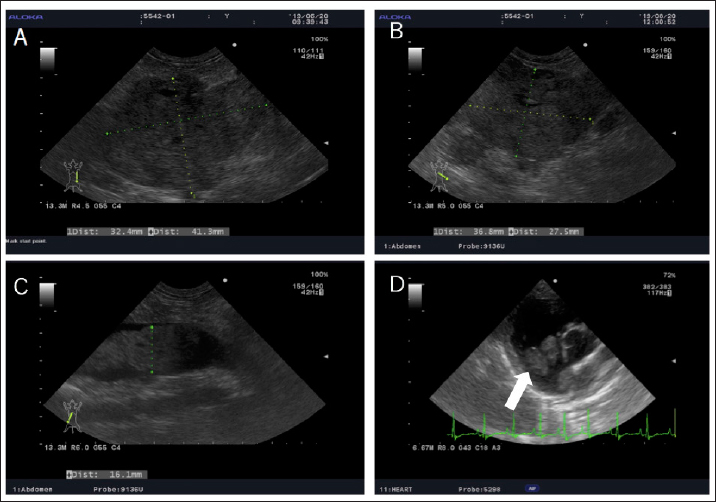

Abdominal echography showed a mixed echogenic intraperitoneal tumor continuous to the left adrenal gland, occupying more than 50% of the abdominal cavity, and the right adrenal gland was not visible. In addition, findings suggestive of tumor invasion into the caudal vena cava were obtained, but the details could not be confirmed because the tumor was too large (Fig. 2A). Therefore, we suspected a huge functional primary AT. The owner was unsure whether to give aggressive treatment or not, so I decided to ask her to come home and think about it. By epidermal curettage test on the dorsal epidermal collarette, we found bacteria thought to be Staphylococci. At the owner’s request, we prescribed cephalexin (Relexepet, 20 mg/kg, PO, BID, Virbac, Kanagawa, Japan) for the dorsal epidermal collarette. On day 9, the dog developed polyuria, but the exact amount of urine passed was not examined. We explained that by knowing the cortisol levels in the body, it might be possible to reduce the volume of the tumor from a medical point of view, and consent was obtained. As the ACTH stimulation test revealed high cortisol levels (pre-stimulation level, 9.5 μg/dl and post-stimulation level, 28.3 μg/dl), we suspected that the intraperitoneal tumor was adrenocortical adenocarcinoma and started mitotane (LYSODREN tablets, Bristol Myers Squibb, New York, NY) administration at 17.4 mg/kg BID according to references (Nelson and Couto, 2011). The changes in cortisol level and mitotane dose are summarized in Figure 1. On day 23, the polydipsia improved and the ACTH stimulation test revealed that the cortisol level decreased (pre-stimulation level, 0.6 μg/dl and post-stimulation level, 1.5 μg/dl). Thus, we thought that the effect of mitotane reduced the AT and reduced cortisol levels. Therefore, the mitotane dose was changed to 34 mg/kg and administered twice a week according to references (Nelson and Couto, 2011). On day 37, as the cortisol levels were found to remain low (pre-stimulation level, 2.0 μg/dl and post-stimulation level, 1.6 μg/dl), mitotane administration was reduced to once a week. On day 63, the dog started showing other symptoms such as a decrease in appetite and a whitish nasal discharge. Direct physical examination revealed a stridor. Although the dog’s general condition did not deteriorate, the cortisol level was higher than last time (pre-stimulation level, 5.5 μg/dl and post-stimulation level, 5.4 μg/dl) and mitotane was administered twice a week at alternate doses of 34 and 17 mg/kg. Palpation also revealed the disappearance of abdominal distension. Abdominal ultrasonography showed that the tumor was entirely isolated around the left kidney, and it had clearly reduced in size compared to that at the initial diagnosis. Nevertheless, tumor formation in the posterior vena cava was clear. A tumor thrombus with a maximum minor axis of 16.1 mm occupying more than 90% of the posterior vena cava was observed. The longest diameter of the tumor thrombus could not be measured because the tumor thrombus was quite long and could not be traced by echo examination (Fig. 2B and C). On day 91, the dog’s appetite had markedly reduced and polydipsia did not recur. However, the post-stimulation cortisol level returned to a high level (22.5 μg/dl). Thus, the mitotane dose was increased to 34 mg/kg and administered twice a week. In addition, as symptomatic treatment, metoclopramide (0.2 mg/kg, PO, BID, Nichi-Iko Pharmaceutical Co. Ltd., Tokyo, Japan), ranitidine (Takepron, 2.1 mg/kg, PO, BID, Glaxo SmithKline plc, London, Greek), and cyproheptadine (Periactin, 0.5 mg/kg, PO, BID, Nichi-Iko Pharmaceutical Co. Ltd., Tokyo, Japan) were prescribed to improve the decreased appetite. On day 101, as the appetite had not recovered and the cortisol level had reduced to 8.5 μg/dl, the mitotane administration was increased to three times a week at 34 mg/kg. On day 115, the general condition remained unchanged, and an ACTH stimulation test was performed. Since the cortisol level was below 2.5 μg/dl both pre and post, the dose of mitotane was reduced again to twice a week. On day 143, decreased appetite was also observed only in the morning, and the cortisol level was 1.5 μg/dl, so the dose of mitotane was continued as before.

However, on day 197, the dog visited because of a severe decline both in appetite and activity, and the left eyeball protrusion. A physical examination revealed external strabismus and protrusion of the left eye and deformity of the fourth premolar to the jawbone. A Grade II/VI systolic murmurs were heard from the right chest wall and left basal portion of the heart. Chest echography revealed wart-like structures in the right atrium (Fig. 2D). Blood tests showed elevated white blood cell count (21,800/μl), elevated C-reactive protein (CRP) (3.7 mg/dl), and mildly elevated GPT (100 U/l). Based on blood tests and echography, the possibility that warts in the right atrium were complicated by bacterial endocarditis could not be ruled out, and there was a high possibility that the nasal discharge was likely due to a bacterial infection, so, enrofloxacin (Baytril, 5 mg/kg, PO, SID, Bayer Yakuhin, Ltd., Osaka, Japan) was prescribed. However, the nasal discharge remained severe and the symptoms of polydipsia recurred. No further treatment was desired by the owner. Finally, the dog died on day 280.

Fig. 2. Echography images of the abdominal and cardiac regions. (A) An intra-abdominal tumor with continuously mixed echogenicity is found in the left adrenal gland, occupying most of the abdominal cavity on day 1. (B and C) At day 63, the size of the tumor mass, particularly, the size of the tumor plug in the posterior vena cava, is clearly reduced. (D) Wart-like structures (shown by an arrow) are also found in the right atrium on day 203.